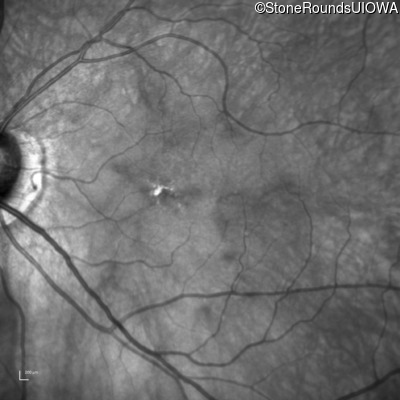

Infrared Fundus Photograph - Right - 20/250

Exemplar